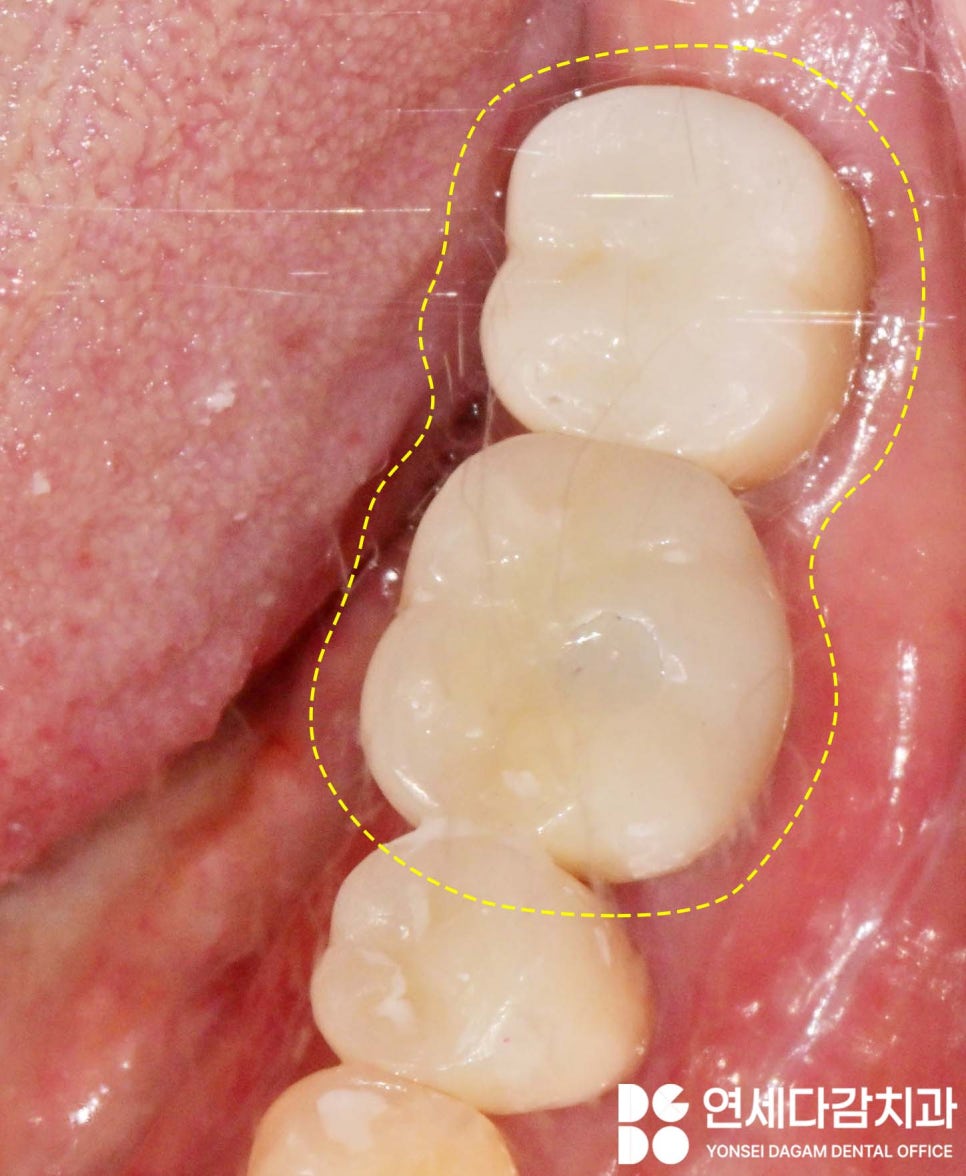

맞는 힐링 어벗트먼트를 체결하고 스캔해서

보철물을 재제작이 완료됩니다.

보철물도 옛날 방법인 PFM 크라운을

지르코니아 크라운으로

교체할 수 있습니다.

이렇듯 전문적인 지식을 통해

형태의 정확한 구분을

할 수 있음으로써

고정체는 그대로 쓰고

옛 보철물만 바꿔 문제를

해결할 수 있습니다.